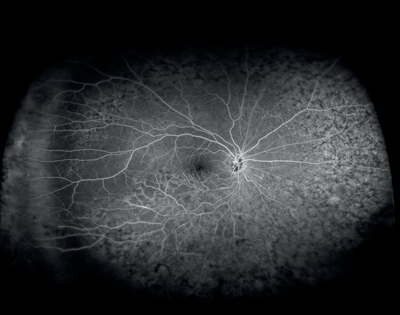

Figures 8 and 9: Case examples from clinical sites: choroidal neovascularisation associated with AMD visualised using fluorescein angiography and optical coherence tomography angiography (images courtesy of Optovue, Inc, CA, USA).

A comparative evaluation of phase-variance OCT (PV-OCT) and FA in normal individuals and patients with age-related macular degeneration (AMD) and diabetic retinopathy (DR) found that phase-variance OCT, which provides volumetric imaging of the retinal vasculature, yields high-resolution imaging of the retinal and choroidal microvasculature that compares well with FA, the current gold standard for retinovascular imaging [2]. Investigators reported that the choriocapillaris was imaged with better resolution of microvascular detail using PV-OCT. Ocular coherence angiography captures retinal vascular changes using split-spectrum amplitude decorrelation angiography [SSADA) to dissect layers of vessels in the retina, and may provide relevant information on the pathophysiology of abnormalities of the retinal vasculature [3].

In a recently-published editorial, Carmen A Puliafito (Los Angeles, USA) described OCT angiography as a true extension of capabilities from spectral-domain OCT, the latter having improved the quality of clinical decision-making, although in reality representing a refinement of the Stratus OCT approach developed by Carl Zeiss Meditec for macular diagnostics [1]. In everyday practice, added Prof Puliafito, most retinal clinicians make their decisions based on a review of the retinal topographic map and several retinal cross-sections of interest. Clinical evaluation of OCT angiography continues, while proponents and retinal specialists alike emphasise its potentially significant clinical potential. Initial published results are promising: OCT angiography can detect capillary nonperfusion as well as or better than fluorescein angiography (FA), and it’s possible to identify microvascular abnormalities associated with leakage.

California-based Optuvue introduced the first commercially available OCT angiography device called AngioVue, providing a non-invasive modality to image ocular microvascular function. This system integrates non-invasive ocular microvascular enhanced imaging with existing Optovue high-speed (70,000 A-scans/sec), widefield, en face spectral-domain OCT technology. AngioVue can be used to image different layers of microvasculature without the need for dye injection as a contrast medium. Conventional OCT allows visualisation of structural change, including drusen and retinal pigment epithelium (RPE) elevation. OCT angiography on the other hand identifies retinal microcirculation in ocular diseases using the intrinsic motion of blood cells in the vessel, helping visualise ocular blood flow and identify microvasculature changes such as choroidal and retinal neovascularisation.